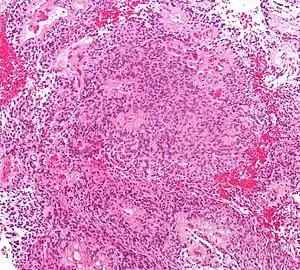

Ependimomas geralmente são tumores de crescimento lento e mais comuns frequentes em crianças e adultos jovens. São classificados como ependimoma clássico (grau II) e ependimoma anaplásico (grau III) . Estes tumores podem ocorrer em qualquer lugar do sistema ventricular ou do canal espinal, entretanto são mais comuns no quarto ventrículo e no canal espinal. Ependimomas são geralmente bem demarcados e com frequentes áreas de calcificação, hemorragia e eventualmente cistos., as células tumorais frequentemente formam as chamadas rosetas ependimais, sinais que praticamente selam o diagnóstico.